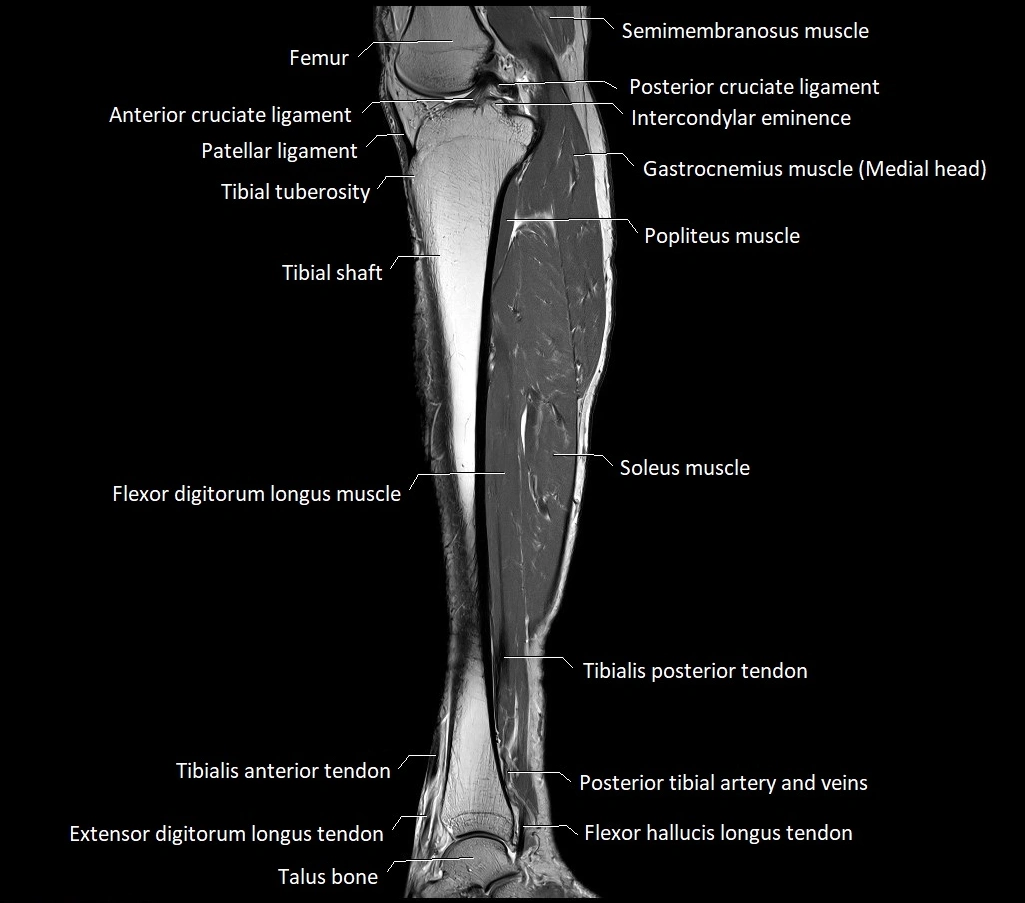

MRI image